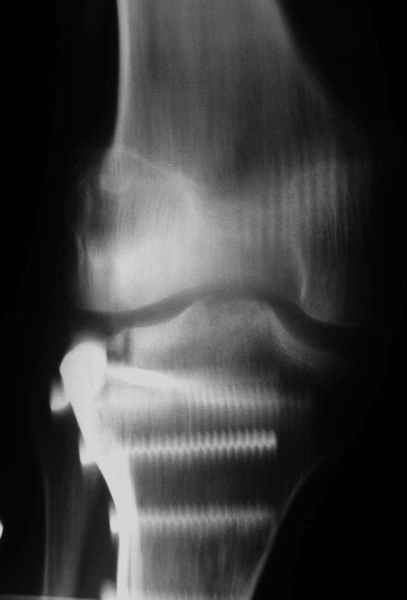

На прием обратилась больная 38 лет. Травма 17.01.2005. 23.01.2005 - операция в одном из стационаров области - остеосинтез мыщелка бедра винтами, Остосинтез мыщелка большеберцовой кости L-образной пластиной.

Август 2005

Иммобилизация лонгетной гипсовой повязкой 2 мес. После прекращения иммобилизации, пр начале ЛФК отмечена нарастающая вальгусная деформация конечности. Рентгенограммы в приложении. Хотелось бы узнать Ваши предложения по тактике лечения